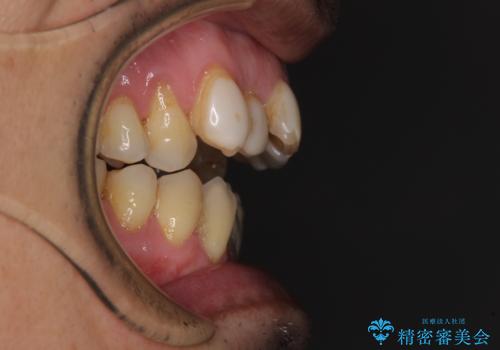

- 長年気になっていた口元を改善したいとのことで来院された患者様です。

外科手術を併用した矯正治療を検討するほどに隙間の空いた開咬と、顕著な叢生が認められました。

開咬の改善には、舌の突出癖改善のためにトレーニングを行いつつ、インビザラインでの矯正治療が大変有効ですが、上顎骨が下顎骨に対して前方位に位置しており、インビザライン単独で治療を行うよりは補助装置とワイヤー矯正で奥歯の咬み合わせを改善してから、開咬改善のためのインビザライン矯正治療を行うこととしました。